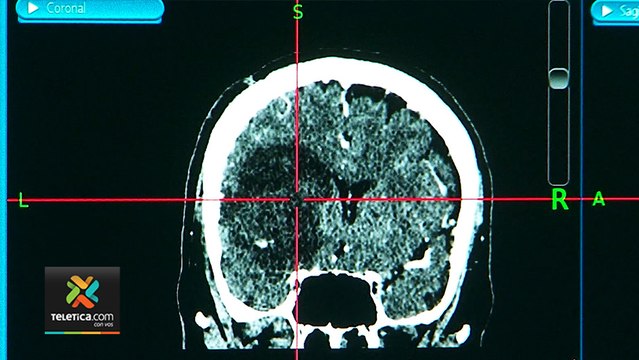

Cooperación en la medicina de la Unión Europea para tratar las 'enfermedades raras'